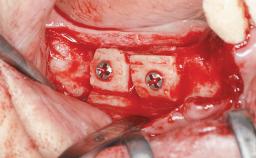

Ridge Preservation and Implant Placement for a Fixed Dental Prosthesis After a Car Accident

It is well known to clinicians that any removal of teeth will, over time, cause the dimensions of the alveolar ridge to be reduced by resorption of the bundle bone and by changes related to external modeling. This development is particularly evident in the crestal region with its thin buccal bone that consists of bundle bone almost entirely. The facial bone will rapidly resorb as blood supply from the periodontal ligament gets disrupted (Araújo and Lindhe 2005). There is no reason why traumatic tooth loss should not have the same consequences. It takes more than achieving implant osseointegration for a treatment outcome to be considered successful. No deficiency of bone or soft tissue is acceptable when an ideal esthetic outcome is the goal. Several articles (Sanz and coworkers 2011; Vignoletti and coworkers 2011) have reported on techniques of improving the alveolar ridge for implant treatment, notably focusing on protecting tissues from resorption.